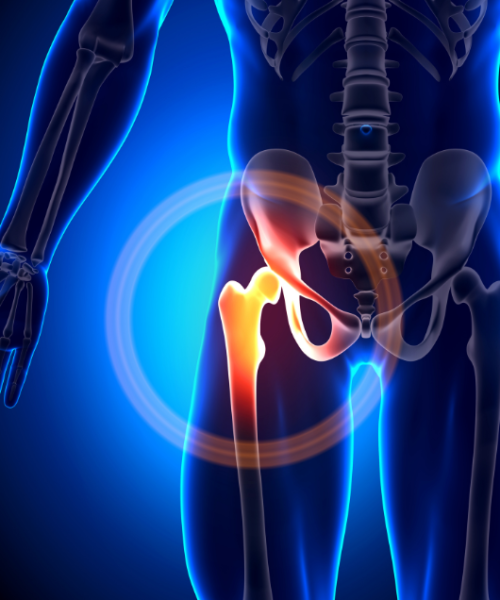

Gre za posledico nepravilnih anatomskih položajev kolka med glavo stegnenice in medenico. Je stanje pred pojavom artroze in je produkt dolgotrajnega zadevanja dela stegnenice ob rob sklepne jamice na medenici zaradi prirojenih anatomskih odstopanj. Poznamo dva tipa utesnitev: tip I (posledica nepravilne oblike glavice stegnenice) in tip II (posledica pregloboke sklepne špranje na medenici in omejitve gibanja).

Gre za posledico nepravilnih anatomskih položajev kolka med glavo stegnenice in medenico. Je stanje pred pojavom artroze in je produkt dolgotrajnega zadevanja dela stegnenice ob rob sklepne jamice na medenici zaradi prirojenih anatomskih odstopanj. Poznamo dva tipa utesnitev: tip I (posledica nepravilne oblike glavice stegnenice) in tip II (posledica pregloboke sklepne špranje na medenici in omejitve gibanja).